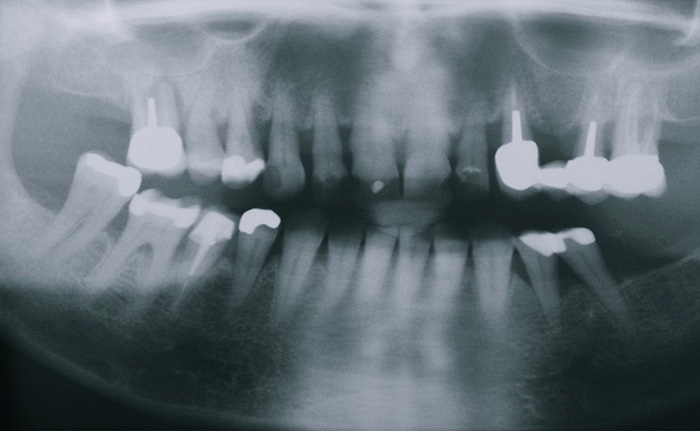

Fallbeispiel

Zum Vergrössern klicken